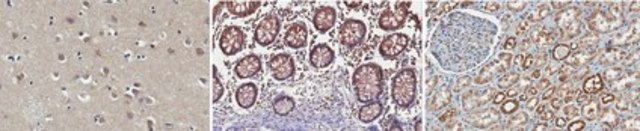

Immunohistochemistry Analysis: A 1:50-250 dilution from a representative lot detected OSBP in human cerebral cortex, small intestine, and kidney tissue sections.